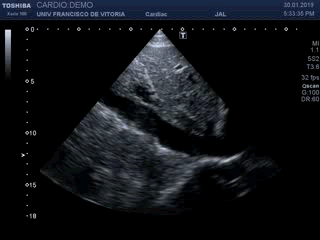

Bien, además del plano 4 cámaras podemos hacer una rotación de la sonda, como siempre, de 90º en sentido horario (ojo, en esta ocasión es en sentido horario) para obtener un “eje corto”. Al igual que en el eje corto paraesternal, podemos ir angulando la sonda para barrer todo el ventrículo y analizar la contracción segmentaria (clip 18). A la hora de describir los segmentos y paredes con movilidad alterada hay que tener cuidado: lo que en el paraesternal es la cara anterior, en el subcostal es la cara inferior o lateralinferior. Pensad dónde se coloca la sonda y desde donde estamos apuntando al corazón.

Well, in addition to the 4 chambers plane we can rotate the probe, as always, from 90º in a clockwise direction (eye, this time in a clockwise direction) to obtain a «short axis». As in the parasternal short axis, we can angulate the probe to sweep the whole ventricle and analyze the segmental contraction (clip 18). At the time of describing the segments and walls with altered mobility, care must be taken: what in the parasternal is the anterior face, in the subcostal is the inferior or lateral inferior side. Think about where the probe is placed and where we are pointing to the heart